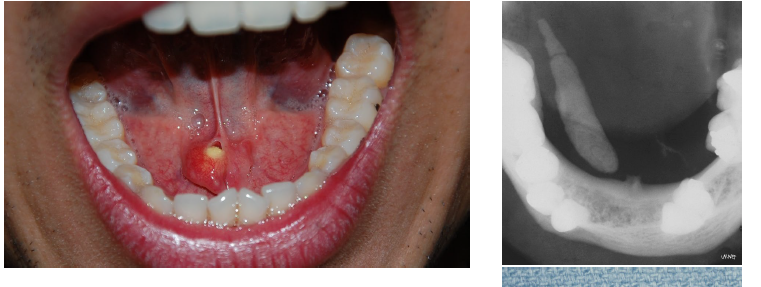

ranula

mucoceles in the floor of the mouth, trauma induced

lateral to the midline, painless swelling

appearance similar to the underbelly of a frog (rana)

possible displacement of the tongue

cervical or plunging

oral

oral ranula

superior to the mylohyoid muscle

cervical or plunging ranula

below the mylohyoid muscle